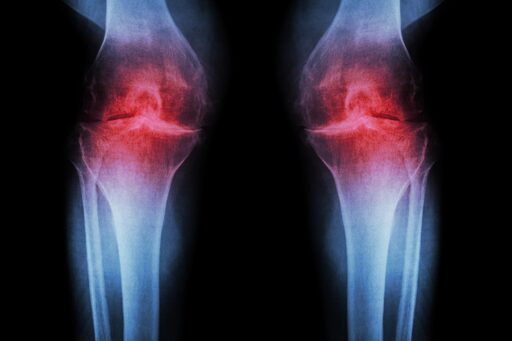

Anti-Aging Injection Regrows Knee Cartilage and Prevents Arthritis

A treatment that blocks an age-related protein restored cartilage in aging and injured joints by reprogramming existing cells rather than using stem cells. Researchers at Stanford Medicine report that blocking a protein linked to aging can restore cartilage that naturally wears away in the knees